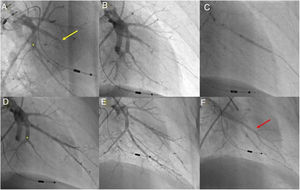

Técnica de angioplastia pulmonar por balãoA BPA foi realizada de acordo com metodologia adotada pelo nosso centro e previamente publicada30 (Figura 1).

Angioplastia pulmonar com balão do segmento A7+8 do lobo inferior esquerdo. A) Angiografia pulmonar seletiva demonstrando oclusão total do segmento A8 (seta amarela) e web na bifurcação do segmento A7 (*); B) Passagem de fio guia Whisper MS (Abbot Vascular, Santa Clara, CA, USA), através da oclusão do segmento A8; C) Dilatação do vaso com balão semicomplacente Pantera Pro (Biotronik SE & Co KG, Berlin, Germany) 4.0/20mm; D) Angiografia pulmonar seletiva demonstrando um bom resultado final no nível do segmento A8 e segmento A7 ainda não abordado (*); E) Após dilatação do segmento A7 no nível da web (*) verifica‐se bom resultado angiográfico final com aumento do fluxo arterial; F) Retorno venoso presente (seta vermelha) na angiografia seletiva final do segmento A7+8 a documentar fluxo pulmonar grau 3.